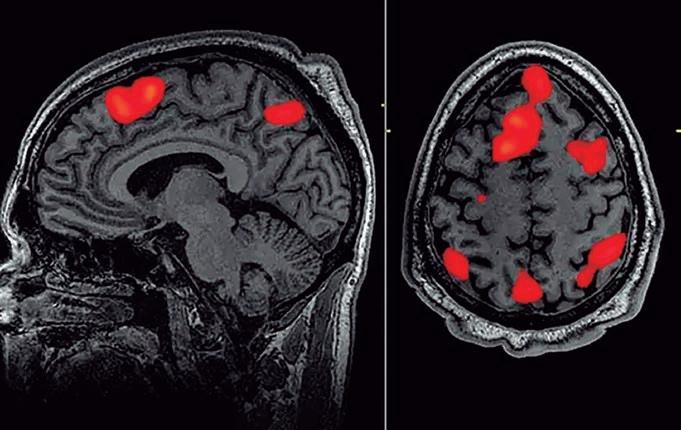

Cientistas usam IA para decifrar palavras e frases de exames cerebrais

Uma interface cérebro-computador que decodifica a linguagem contínua de gravações não invasivas teria muitas aplicações científicas e práticas. Atualmente, no entanto, decodificadores de linguagem não invasivos só podem identificar estímulos entre um pequeno conjunto de palavras ou frases. Cientistas, apresentaram um decodificador não invasivo que reconstrói a linguagem contínua a partir de representações semânticas corticais registradas por ressonância magnética funcional (fMRI). Dadas novas gravações cerebrais, este decodificador gera sequências de palavras inteligíveis que recuperam o significado da fala percebida, da fala imaginada e até mesmo de vídeos silenciosos, demonstrando que um único decodificador pode ser aplicado a uma variedade de tarefas.

O decodificador foi testado em todo o córtex e descoberto que a linguagem contínua pode ser decodificada separadamente de várias regiões. Como as interfaces cérebro-computador devem respeitar a privacidade mental, foi testado se a decodificação bem-sucedida requer cooperação do sujeito e descoberto que a cooperação do sujeito é necessária tanto para treinar quanto para aplicar o decodificador. As descobertas demonstram a viabilidade de interfaces cérebro-computador de linguagem não invasiva.

O decodificador baseado em IA que pode traduzir a atividade cerebral em um fluxo contínuo de texto foi desenvolvido, em uma inovação que permite que os pensamentos de uma pessoa sejam lidos de forma não invasiva pela primeira vez.

A IA decifra palavras e frases de exames cerebrais (leitura não invasiva da mente), transformando pensamentos em texto. A neuro tecnologia emergente pode algum dia ajudar pacientes paralisados a se comunicarem, aumentando a perspectiva de novas maneiras de restaurar a fala naqueles que lutam para se comunicar devido a um derrame ou doença do neurônio motor, mas também pode aumentar as preocupações com a privacidade

O decodificador pode reconstruir a fala com incrível precisão enquanto as pessoas ouvem uma história – ou até mesmo silenciosamente imaginam uma – usando apenas dados de ressonância magnética funcional.Os sistemas de decodificação de linguagem anteriores exigiam implantes cirúrgicos, e o avanço mais recente levanta a perspectiva de novas maneiras de restaurar a fala em pacientes que lutam para se comunicar devido a um derrame ou doença do neurônio motor. Alexander Huth, um neurocientista que liderou o trabalho na Universidade do Texas em Austin, disse: “Ficamos meio chocados com o fato de funcionar tão bem.

Vídeo mostra uma visão do córtex cerebral de uma pessoa. As áreas rosa têm atividade acima da média; áreas azuis têm atividade abaixo da média. O estudo usou ressonância magnética funcional (fMRI) para decodificar os pensamentos das pessoas Assista o GIF: www.bit.ly/41p5W8j Grande modelo de linguagem, GPT-1, um precursor do ChatGPT